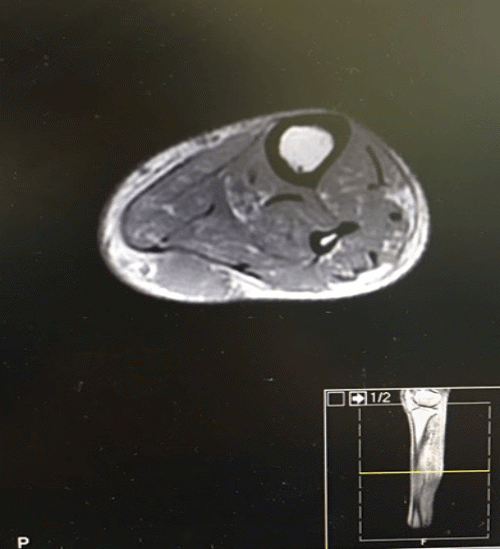

Further workup revealedan additional soft tissue mass that measured 3.5 × 2.5 and was located in the left posterior calf cm. As a result of the preliminary pathological diagnosis of the original mass, which indicated it to be a highly malignant tumor, the new finding required further workup. Once the patient stabilized, an MRI of the left lower extremity was performed. These images revealed no evidence of osteomyelitis but did identify a 3.5 × 1.7 × 2.5 cm subcutaneous cystic structure in the left posterior calf (Figure 3).

Figure 3. Left Calf Metastasis: 3.5 x 1.7 x 2.5 cm Subcutaneous Cystic Structure. Published with Permission